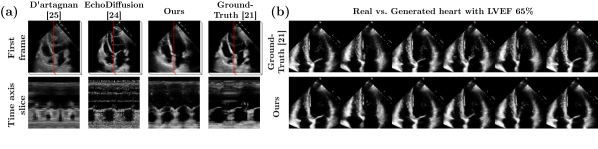

To evaluate the LVDM, we use generative metrics FID, FVD 16, FVD 128 and IS. We generate 2048 videos with 192 frames for Dyn and 128 frames for Ped. We use two types of latent images to condition the video generation: (1) encoded real images, and (2) LIDM-generated latent images. For the Dyn dataset, Table 3 shows that our LVDM performs better when using encoded real images than when using LIDM-generated latent images. Nevertheless, our LVDM using LIDM-generated latent images achieves competitive results compared to the state-of-the-art echocardiogram generation method [24], in terms of image quality (FID) and video quality (FVD). Qualitatively, Figure 2 (b) shows that our LVDM can generate videos which are indistinguishable from real ones. For the Ped dataset, Table 3 shows that our LVDM achieves good overall performance. Regarding video generation sampling time, our method (2.4s for 64 frames) is two orders of magnitude faster than the state-of-the-art method [24] (279s for 64 frames). In addition, with the proposed video stitching strategy, we can generate infinitely long temporally-consistent videos. To demonstrate the scalability of our method, we generate a 10-minute-video (19,200 frames at 32 fps) in 14 minutes on a A100 GPU.

Refer to caption

Figure 2: (a) Temporal consistency of our generated videos against previous works [24, 25] and the real data [21]. (b) Qualitative results of our generated videos against the real data [21], animating the same heart with the same LVEF.

EchoNet-Synthetic: We generate EchoNet-Synthetic (Syn) with our video generation pipeline. Syn contains three sub-datasets, corresponding to the three real datasets. Each sub-dataset has the same number of videos as its corresponding real dataset, and the number of frames in each video is the average number of frame in the corresponding real dataset. The visual quality of Syn is competitive with previous state-of-the-art, and is indistinguishable from real data (Figure 2 (a) top row). In terms of temporal consistency, Syn outperforms all previous works, and matches the real data (Figure 2 (a) bottom row).